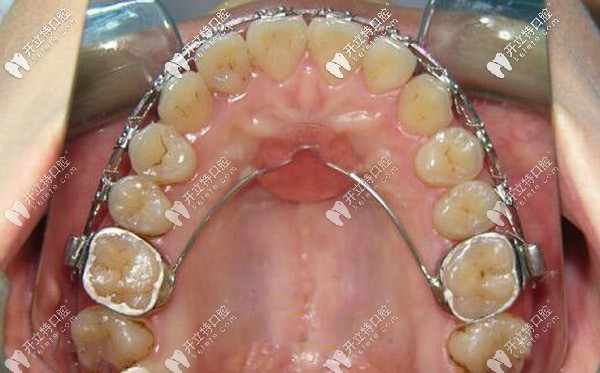

腭側(cè)nace弓矯正圖片▼

腭側(cè)nace弓矯正圖片

與橫腭桿一樣將上頜兩側(cè)磨牙連接在一起,與橫腭桿不同的是Nance托是以硬腭作為支抗,使用1.5mm或1.2mm的不銹鋼絲彎制,鋼絲彎向腭前部,在腭穹隆處制作直徑5~8mm的腭托,與腭黏膜緊密接觸,當(dāng)磨牙受力時(shí),腭托限制了磨牙的移動(dòng),從而加強(qiáng)了后牙的支抗。